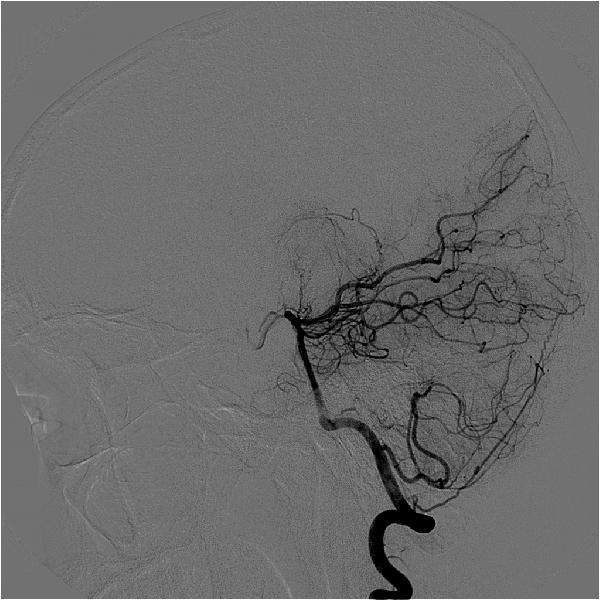

在人体中,动脉负责将富含氧气的血液从心脏输送到大脑,静脉则将贫氧的血液带回肺部和心脏,然而血管畸形就像是一撮粗细不一缠绕在一起的毛线团,损害了动静脉血液流通这一重要的过程。

血管的畸形可以在你身体的任何部位发生,但最常发生在大脑或脊柱中,其中脑血管畸形更是能对身体能造成例如脑损伤和中风等严重的危害,是指脑血管发育障碍而引起的脑局部血管数量和结构异常,并对正常脑血流产生影响。目前造成脑血管畸形的原因尚明确,大多数人天生就会患有脑血管畸形,呈现非肿瘤性发育异常。

2、栓塞术—栓塞术也称栓塞治疗(embolotherapy),是经动脉或静脉内导管将塞物有控制地注入到病变器官的供应血管内,使之发生闭塞,中断血供,以期达到控制出血、治疗肿瘤和血管性病变以及消除患病器官功能的目的。栓塞术是介入治疗中的重要技术,血管内栓塞术的创伤性较传统手术小,并且能合适的减小脑血管畸形的的大小以及出血的可能性,将血液重新导向正常脑组织来减少中风样症状,使手术更顺利。